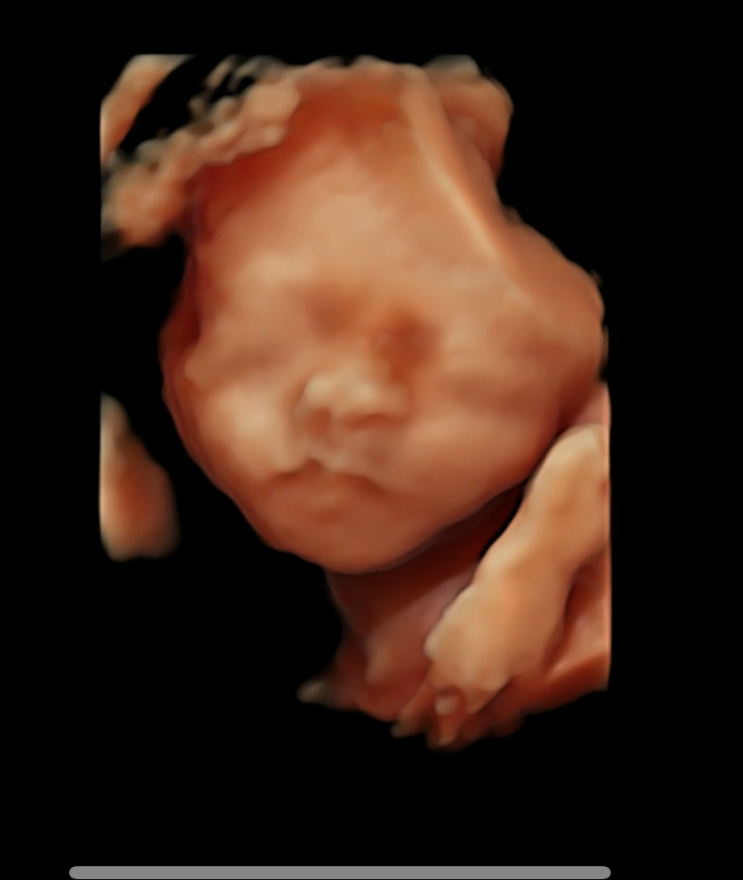

임신중일기_8. 34주차 초음파. 머리가 크..크다!! 입체초음파 얼굴보기

한나산부인과에 꾸준히 다니는 중!! 34주차 초음파, 오늘도 병원을 갔다왔지만.. 어떻게 2주만에 400g이 늘...